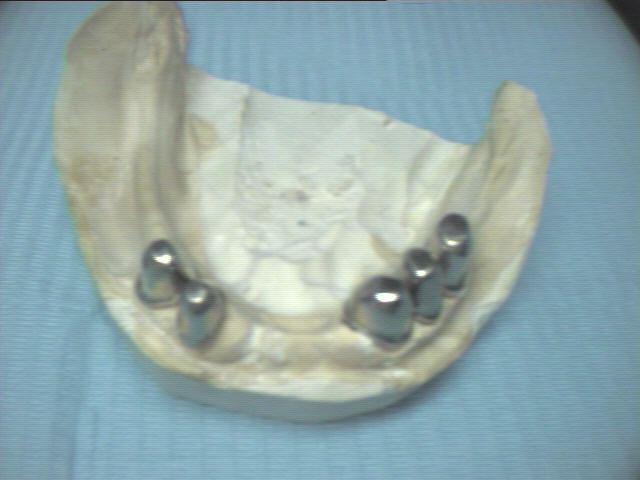

Teleskopprothese

(Deckprothese) mit 5 Teleskopkronen im Unterkiefer

Ein herausnehmbarer Zahnersatz auf 5 eigenen Zähnen. Die ersten Kronen (Primärkronen) sowie die zweiten Kronen (Sekundärkronen) wurden aus Edelstahl (kostengünstig) angefertigt.

Heute wird für Teleskopkronen statt Edelstahl lieber Zirkon genommen, weil die Kronen passgenauer sind.